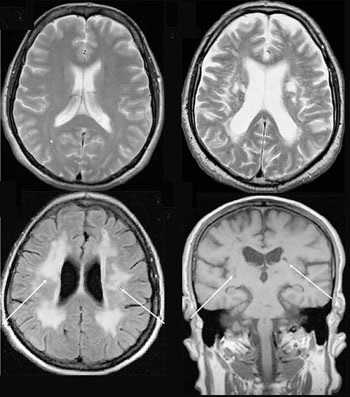

- Томография. Для определения стадии заболевания и получения более полных данных о структуре, размере и расположении фибросаркомы при необходимости назначают КТ и МРТ.

Магнитно-резонансная томография или МРТ - это сфокусированный метод, который проводит очень детальное обследование. Диагностическая точность МРТ превышает УЗИ и во многих случаях КТ, за исключением сканирования полых органов (легких, желудка, кишечника) и костей. МРТ является золотым стандартом диагностики:

- заболеваний головного и спинного мозга;

Принцип работы МРТ основан на эффекте ядерного магнитного резонанса. МР томограф в своей конструкции имеет мощный магнит, который создает магнитное поле, и датчик, который подает радиочастотные сигналы. В такой ситуации протоны атомов водорода начинают колебательные движения, выделяя при этом импульсы. Их улавливает компьютер томографа и преобразовывает в трехмерные изображения. Чем больше воды содержится в клетках ткани, тем детальней получается ее изображение. Поэтому на МРТ хорошо отображаются органы с большим содержанием воды: МРТ головного мозга, МРТ спинного мозга, МРТ глазных орбит, МРТ органов малого таза, МРТ позвоночника, МРТ суставов, и плохо визуализируются органы с большим содержанием воздуха МРТ органов грудной клетки или кости.

МРТ будет эффективно при исследовании опухолей, мозга и аномалиях развития сосудов.

Магнитно-резонансная томография

В основе МРТ лежит явление магнитного резонанса, основанного на переизлучении радиоволн, взаимодействующих с атомами водорода, в избытке содержащимися в организме человека. Эти переизлученные электромагнитные волны улавливаются датчиком МР-томографа, усиливаются и в виде цифровых изображений появляются на экране монитора. Это безвредный и абсолютно безопасный для здоровья человека метод лучевой диагностики, так как в основе получения изображения отсутствует рентгеновское излучение, поэтому МРТ можно проходить неограниченное количество раз, с любым интервалом.

Существенное преимущество МР-томографии перед КТ заключается в том, что она не противопоказана беременным во II и III триместре и совершенно безопасна для детей. В МРТ исследуемая область сканируется в трех проекциях, что позволяет врачу-рентгенологу в полной мере оценить состояние тканей и органов исследуемой области, а высокая контрастность изображения и пространственное разрешение позволяют визуализировать серое и белое вещество головного мозга, оценивать состояние костного мозга и мягких тканей различной локализации. Кроме того, метод МРТ позволяет получать изображения сосудов головного мозга и сосудов шеи без введения контрастного препарата.

Мы также всегда делаем КТ пациентам с подозрением на нарушение мозгового кровообращения, исследование позволяет не только подтвердить диагноз, но и оценить «масштаб» поражения и выработать верную тактику. Назначают его при патологии почек, в частности, при наличии камней. На томографе можно увидеть их расположение, оценить плотность и структуру, а значит, принять решение об операции или выборе консервативных методов. МРТ имеет преимущества при изучении патологий суставов, для диагностики заболеваний головного мозга, спинного мозга, органов малого таза.